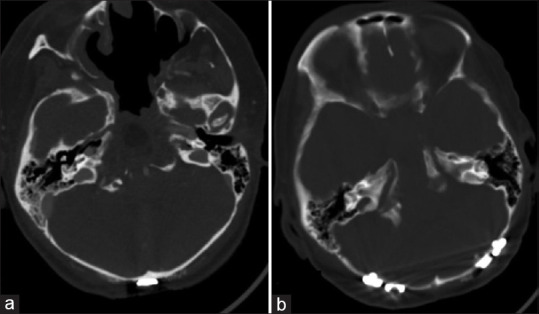

Instability of the occipitocervical junction may compress neural elements, resulting in progressive disability. After the Kickstand Rod technique was developed to correct for thoracolumbar scoliosis, the Candy Cane construct was developed for chin-on-chest deformity at the cervicothoracic junction as a similar three-rod approach. Demonstrated is a four-rod iteration utilized to stabilize the occipitocervical junction and correct condylar instability, termed the Catcher's Mitt technique. A 34-year-old woman with Goldenhar syndrome, hemihypertrophy, and a complex neurosurgical history including Chiari decompression, clival chordoma resection, and a previous cervical fusion presented with quadriparesis, dysphagia, and bilateral upper extremity paresthesias. She was found to have pontomedullary and craniocervical instability with occipital translation and subluxation of the atlantooccipital joint, contributing to her neurological decline. A single midline incision and periosteal dissection exposed her prior O to C6 instrumented fusion. Existing rods were replaced, and a third plate-rod was placed on the right from O to C6. On the left, a fourth plate rod was positioned from C1 to C6. Four top-loading connectors secured the accessory rods to the primary construct. After confirming a stable lordotic alignment, distraction across the accessory rods was used to assist with coronal correction. The Catcher's Mitt construct improved this patient's sagittal and coronal plane deformity. Postoperatively, the cervical sagittal vertical axis improved by 25 mm and the chin-brow angle by 20 mm. Significant improvements in functional status were achieved at 2-year follow-up. A one-stage posterior approach with construct augmentation using third and fourth accessory rods can correct atlantooccipital subluxation following failed occipitocervical fusion.